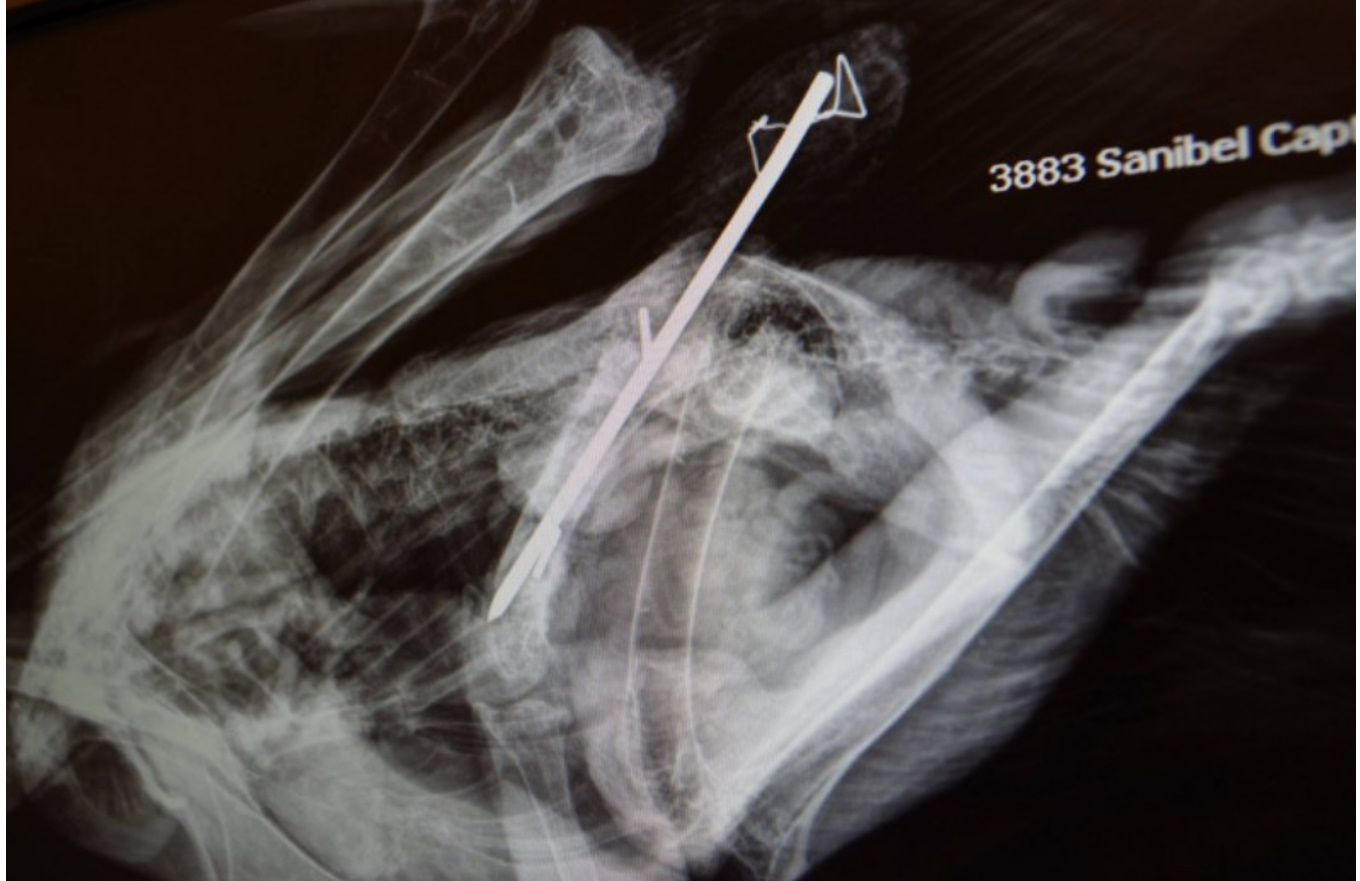

Edytce wykonano ponownie prześwietlenie RTG. Wykazało prawidłowo ułożoną "szpilkę", właściwie złożoną kość.

Dr Barron ostrożnie określiła stan Edytki jako zadowalający, jednocześnie zaznaczając, że rehabilitacja potrwa dość długo.

Wczoraj Edytce ponownie wykonano RTG . Miejsce złamania wygląda dobrze, szpilka jest w miejscu wszczepienia. Edytka wstaje i próbuje chodzić. Poziom białka jest nadal niebezpiecznie niski.

Dr Barron ogląda zdjęcie RTG Edytki

Są wyniki badań Edytki. Wskazują one na to, że antybiotyki działają właściwie i skutecznie zwalczają infekcję w rannej kości. Bieliczka będzie teraz przez następne kilka tygodni otrzymywać doustnie ( dodziobnie :D) bezpieczniejsze antybiotyki , by zwalczyć infekcję do końca. Zdjęcia RTG wskazują na ogólną poprawę . Edytka nadal je samodzielnie ,jest bystra, ciekawa i prawidłowo reaguje na bodźce. Nadal będzie otrzymywać odżywki wspomagające regenerację kości, mięśni .